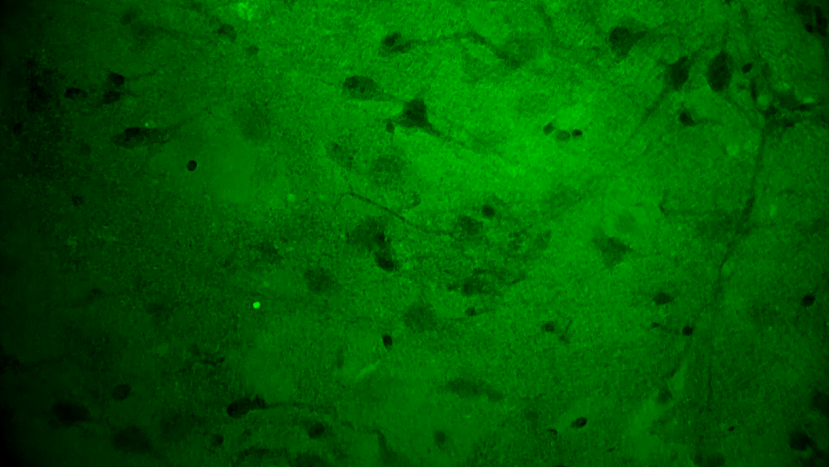

关颅期间,专家团队将其余3块瘤体组织应用EndoSCell®扫查以观察肿瘤细胞形态,无一例外,3块组织的细胞图像均符合“核异型性明显、分布密集且不规则”的肿瘤形态特征,其中一块还意外发现了清晰的神经元细胞。EndoSCell®高清直观的细胞图像给专家们留下了深刻印象,参与本次手术的张帅专家表示有合适机会或将尝试在体应用。

神经元细胞:神经纤维束清晰、密度低